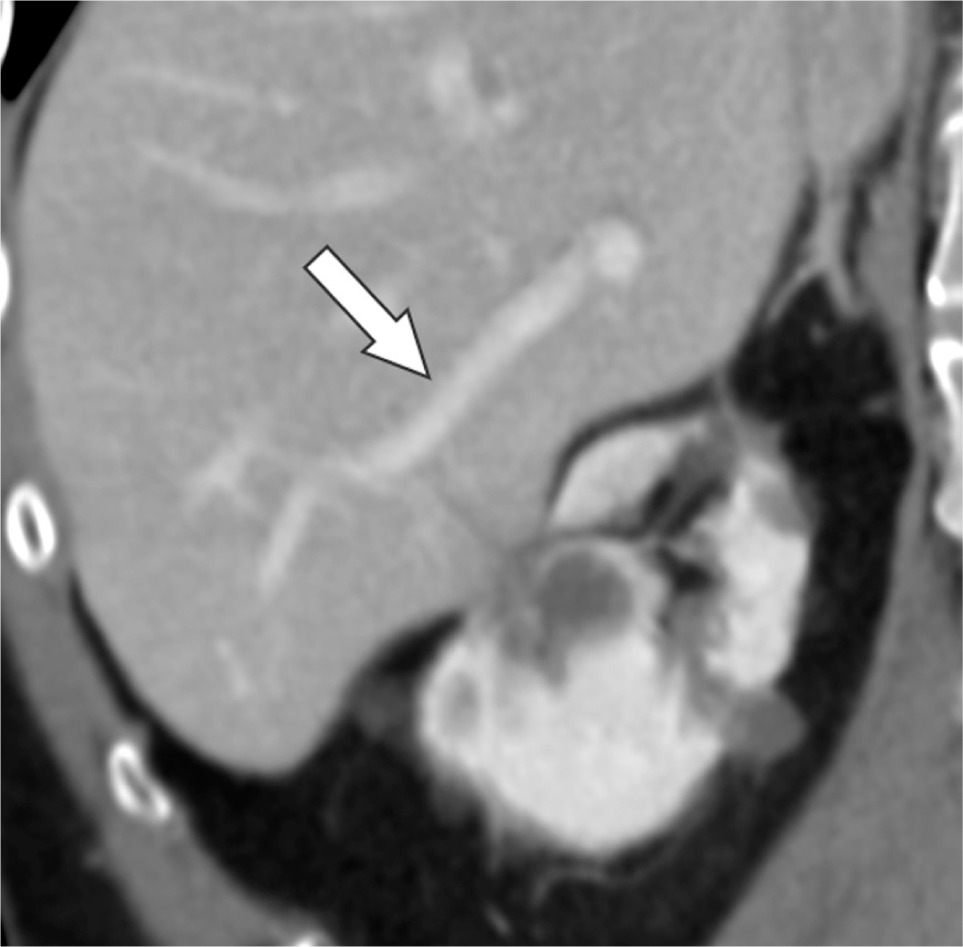

Figure 1: Oblique coronal contrast-enhanced CT before cryoablation reveals the normal liver parenchyma and patent portal vein branch (arrow).

Figure 2: Oblique coronal contrast-enhanced CT 2 days after cryoablation reveals the ablated liver parenchyma (arrowhead) and portal venous thrombus (arrow).